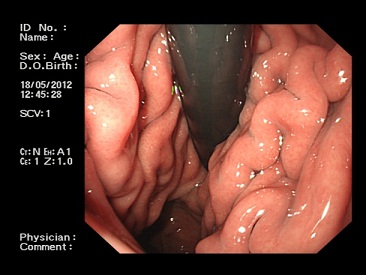

1.胃鏡檢查 Mallory-Weiss病變多位于食管-胃結(jié)合部,因此胃鏡檢查診斷價(jià)值優(yōu)于食管鏡檢查。

Millet和Hirschowitz(1970)報(bào)道的23例Mallory-Weiss綜合征中,19例經(jīng)胃鏡檢查而確診,其中12例在內(nèi)鏡下可見(jiàn)胃食管結(jié)合部黏膜有縱行撕裂傷,占55%;7例(30%)在內(nèi)鏡下看不到食管及胃黏膜有明顯損傷,但仍然可見(jiàn)出血來(lái)自食管-胃結(jié)合部;3例在做胃鏡檢查時(shí)因胃內(nèi)充滿血液,檢查不滿意,無(wú)法作出診斷;1例未做胃鏡檢查,手術(shù)探查時(shí)發(fā)現(xiàn)食管下段黏膜撕裂并發(fā)出血,由此可見(jiàn)Miller和Hirschowitz報(bào)道的23例:Mallory-Weiss綜合征中,85%(19/23)都是經(jīng)胃鏡檢查后才作出診斷的,胃鏡檢查對(duì)這一綜合征的診斷具有其他檢查不能代替的診斷價(jià)值,只要無(wú)禁忌證,都應(yīng)首先做胃鏡檢查。